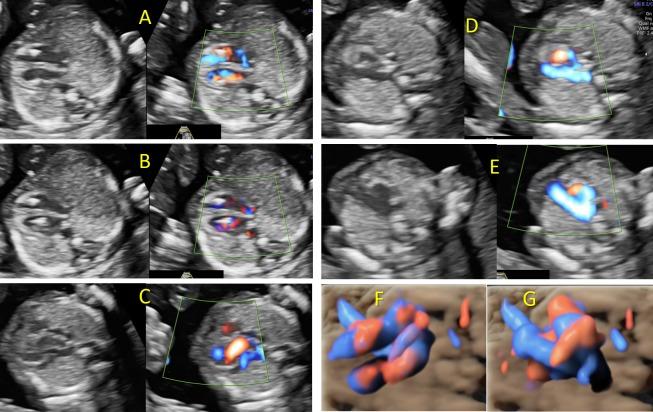

Early onset fetal growth restriction (EO-FGR) is associated with significant feto-maternal complications, therefore efforts should be made to identify the causes and the potential outcome of the pregnancy. Some of the pitfalls in first-trimester imaging of the fetal anomalies are related to the inadequacy of the examination, because of the fetal position and limited clarity in relation to the size of the structures being examined. In this paper we present a case where careful ultrasound scan follow-up and the use of both approaches transabdominal and transvaginal were useful to complete a detailed structural evaluation as part of the diagnosis, management and prognosis of a fetuses diagnosed with EO-FGR in the first trimester and a triploidy with atypical ultrasound features.

早发型胎儿生长受限(EO-FGR)与严重的母婴并发症相关,因此应努力确定其病因及妊娠的潜在结局。孕早期胎儿畸形超声检查的一些陷阱与检查不充分有关,这是由于胎儿体位以及与被检查结构大小相关的清晰度受限所致。在本文中,我们介绍了一个病例,对于一名在孕早期被诊断为EO-FGR且伴有非典型超声特征的三倍体胎儿,仔细的超声扫描随访以及经腹和经阴道两种检查方法的联合使用,有助于完成详细的结构评估,作为诊断、管理及预后判断的一部分。